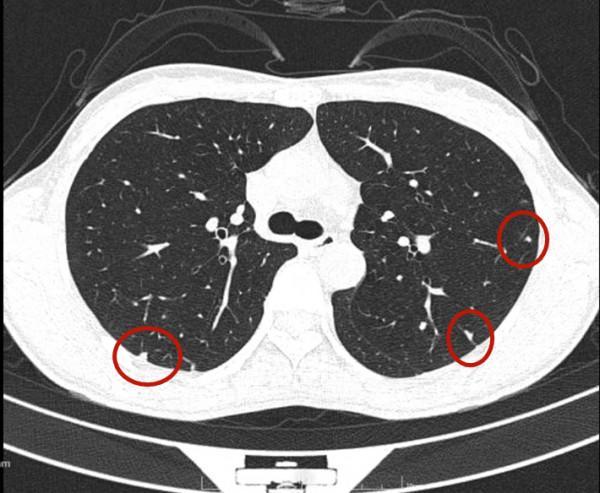

今天一位網路問診病人,女性,34歲,檢查發現雙肺多發實性結節,在當地醫院不同科室就診意見不一,再到不同醫院胸外科就診,意見也不一。怎麼辦呢?是結核、免疫疾病、風溼,還是腫瘤轉移?要不要手術活檢?我們來瞧瞧她的病例:

可見她體檢發現,沒有症狀,看了呼吸科、風溼免疫科、結核科以及胸外科,而且還看了三家三甲醫院的胸外科,但意見莫衷一是。其CT是如何的呢?來看看:

那麼多結節,基本上都是實性,分佈兩肺,形態不似圓形或類圓形的轉移瘤。是什麼呢?我們是不是一定要弄明白到底是什麼病?其實我覺得有時並不一定要弄清楚,所以我回復的意見如下:我認為我們看病,有時候可以從結果來反推,從而考慮是不是干預治療。比如這個病例的兩肺多髮結節,我看沒有一個是主病灶,也就是說“明顯考慮惡性的,其他考慮是這個病灶轉移的”這種樣子。那麼這些實性小結節,可能是:1、良性結節:包括慢性炎,纖維增生、肺內淋巴結、風溼結節、肉芽腫、隱球菌等各種可能性。但只要是良性,不處理不影響生命,也沒什麼不舒服,只需關注著,定期複查就可以了;2、腫瘤多發轉移:不管原發灶在哪裡,如果兩肺這麼多轉移,你再怎麼治療,預後也不好,現在還不是典型的腫瘤,也未見明顯的原發部位,遲點有進展再考慮又有多少區別呢?3、結核:即使真是結核,沒有明顯症狀的情況下,很多人自己得過結核也不自知,意思是說,如果痰找結核菌陰性,不是活動性肺結核,沒有症狀,不治療也沒什麼關係,也是隻需要定期複查。所以你的病例,我的意見是:1、形態數目不像惡性;2、不需深究到底是什麼;3、把診斷交給時間來決定,建議每4-6個月複查平掃,有變化時展再考慮活檢或干預,否則先不去管它。